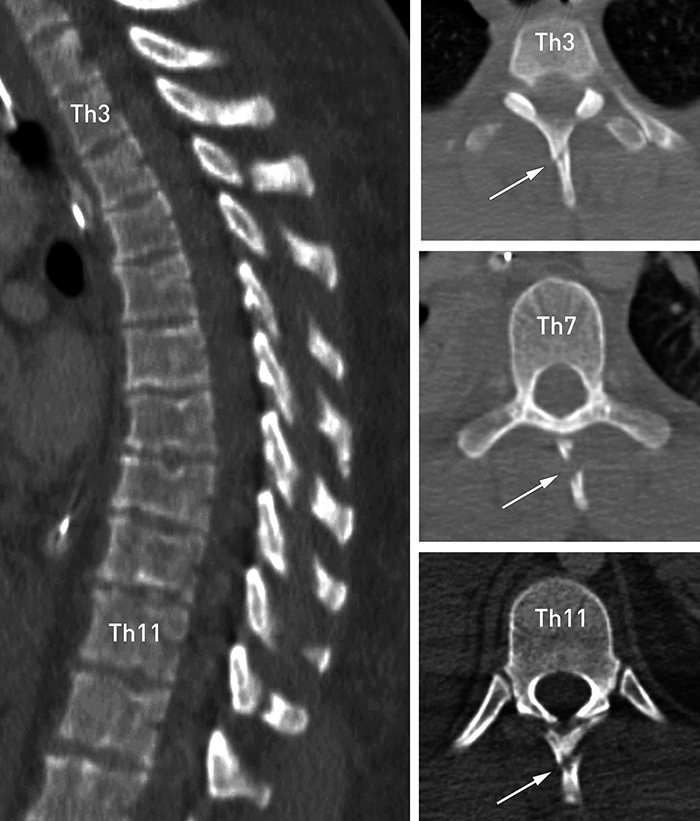

En mann i 20-årene pådro seg multiple skader i en snøscooterulykke. Ved undersøkelse i akuttmottaket hadde han 9 på Glasgow Coma Scale (GCS 9), sterke smerter og ømhet over torkalcolumna, men ingen fokale nevrologiske utfall. Traume-CT avdekket cerebrale kontusjonsblødninger, frakturer i skallebasis, skulderblad og ribbein og pneumothorax som følge av ribbeinsbruddene. I tillegg ble det påvist totalt ni isolerte frakturer av processus spinosi, også kalt «clay-shoveler’s fracture», fra Th3 til Th11. Klinisk undersøkelse og bildediagnostikk ga ikke mistanke om ytterligere skader i columna. Ryggfrakturene ble behandlet konservativt: smertestillende medikamenter og immobilisering i seks uker. Etter dette ble han fullt mobilisert og smertefri.

Grøftegraverfraktur (clay-shoveler’s fracture) er en historisk yrkesskade som fikk mye oppmerksomhet i 1930-årene under konstruksjonsarbeidet av motorveier blant annet i Tyskland (1). Bruddene oppsto hos veiarbeiderne som spadde tung masse. I dag forekommer denne typen brudd relativt sjelden og er sannsynligvis en ofte oversett skade, som hovedsakelig er assosiert med trafikkulykker. Brudd i flere nivåer (> 5) er svært sjeldent og kun to tilfeller er, så langt vi kjenner til, rapportert i litteraturen tidligere (2). Frakturen kan oppstå ved direkte slag mot processus spinosus eller ved indirekte traume. En ballistisk bevegelse med kraftig ekstensjon, fleksjon eller rotasjon av cervikotorakalcolumna kan føre til avrivningsskade av ligamentum supraspinosus. Frakturen er vanligvis stabil og ikke forbundet med nevrologiske utfall (1, 2). Man må likevel utelukke andre columnaskader. Vanligvis behandles skaden konservativt (1, 2), men i enkelte tilfeller kreves det kirurgisk ekstirpasjon av beinfragmenter for smertelindring.